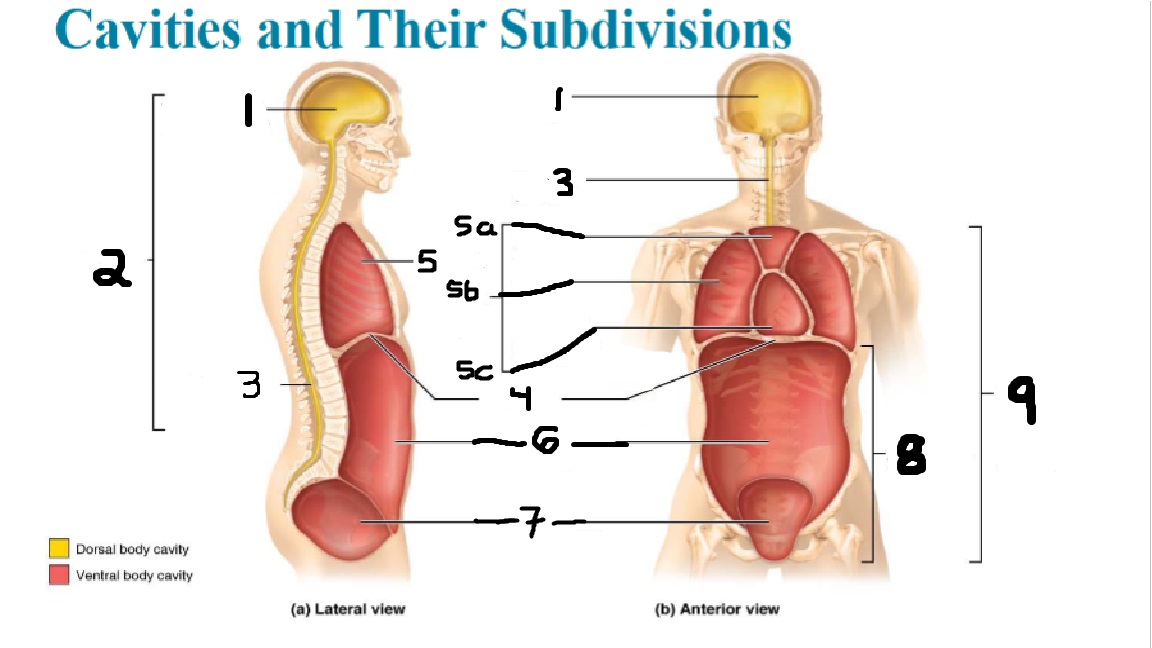

What cavities are part of the dorsal cavity?

The cranial and the Spinal (vertebral) cavities

What kind of cavity is labeled 2?

The dorsal body cavity (containing the cranial and spinal cavities)

What is the purpose of the dorsal cavity?

protects the nervous system

What is the main organ encased by the cranial cavity?

the brain

What cavity is labeled #1?

The cranial cavity

What is the main organ encased by the vertebral cavity?

the spinal cord

What is another word for the vertebral cavity?

the spinal cavity, or the spinal canal

What body cavity is labeled 3?

the vertebral cavity.

What cavities are included in the ventral cavity?

the thoracic, abdominal, and pelvic cavities.

What body cavity is labeled #6?

the abdominal cavity.

What are the main organs of the abdominal cavity?

the digestive organs such as the stomach, intestines, spleen and liver

What cavities are included in the Abdominopelvic cavity?

the abdominal cavity and the pelvic cavity

What body cavity is labeled #8?

The Abdominopelvic cavity

What does the diaphragm separate?

the thoracic and the abdominal cavities

What is labeled #4?

the diaphragm

What organs does the pelvic body cavity contain?

urinary/reproductive organs and rectum

What is labeled #7?

the pelvic cavity

What does the thoracic cavity encase?

the heart and the lungs

What is labeled #5?

the thoracic cavity

What part of the thoracic body cavity is labeled 5a?

superior mediastinum

What part of the thoracic body cavity is labeled 5b?

pleural cavity

What part of the thoracic body cavity is labeled 5c?

pericardial cavity within the mediastinum

What body cavity encloses the heart?

the pericardial cavity.